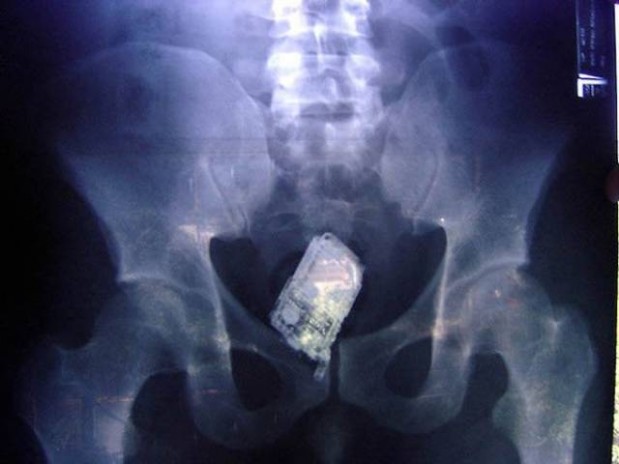

#4 Puhelin